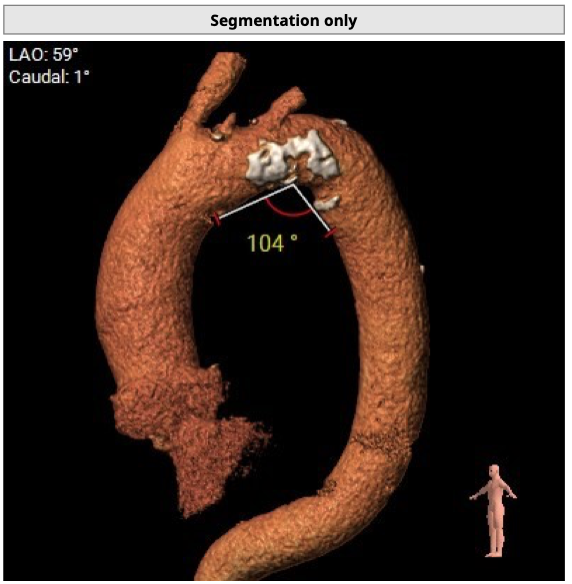

升主动脉长度:66.8mm,瓣环水平夹角44度